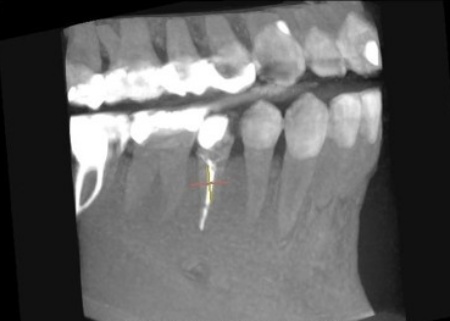

拝見したところ、右下奥歯(第2小臼歯)には保険診療の白い被せ物であるCAD/CAM冠が装着されていましたが、破折して外れている状態でした。

右下奥歯を詳しく検査をした結果、過去に細菌感染した神経を取り除いてから薬を詰める「根管治療」が行われていることがわかりました。

ただ、その手前の右下奥歯(第1小臼歯)では、歯の内部に細菌が侵入して炎症が生じており、歯根の先に膿が溜まる根尖(こんせん)病巣を発症しています。

このまま放置すると、歯根の周辺組織にまで感染が広がって歯を支える骨が溶け、将来的に歯を失うリスクがあります。

以上のことから、根尖病巣を早急に治療し、新しく被せ物を作り直す必要があると診断しました。

まず、血液や唾液に含まれる細菌が根管内に入るのを防ぐため、ゴム製のシートであるラバーダムで患部周辺を覆って治療部位だけを露出させ、マイクロスコープで確認しながら感染部位を丁寧に除去しました。

根管内が清潔になったら、再び細菌が入り込まないようにしっかりと薬を詰めて封鎖後、レントゲン撮影で根尖病巣の治癒を確認しました。